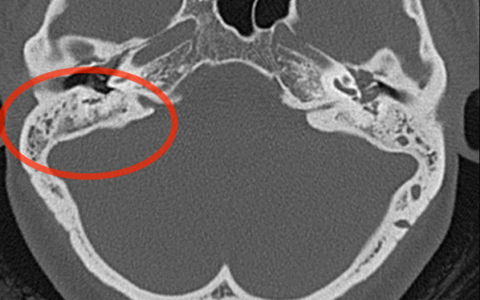

МСКТ височной кости — КТ-картина образования пирамиды правой височной кости с костно-деструктивными изменениями, правостороннего среднего отита. Образование на МСКТ височной кости отграничено сверху базальным завитком улитки и преддверием, снизу — яремной веной, медиально — твердой мозговой оболочкой задней черепной ямки, латерально — гипо- и мезотимпанумом, спереди — вертикальной частью внутренней сонной артерии, сзади — сагиттальным ПК, внутренним слуховым проходом (рис. 1). Рис. 1. МСКТ височной кости (правое ухо). КТ-картина инфралабиринтной холестеатомы пирамиды височной кости (а — аксиальная проекция, б — коронарная проекция).